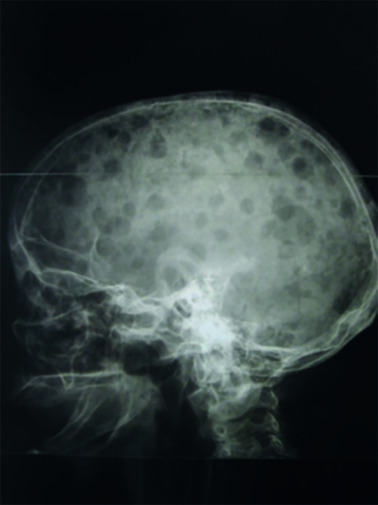

Les plasmocytes myélomateux désorganisent l’homéostasie du stroma médullaire, en activant les ostéoclastes et en inhibant les ostéoblastes. Ce déséquilibre entre résorption et fabrication osseuse conduit à l’apparition de lésions ostéolytiques. Elles sont classiquement « à l’emporte-pièce », principalement dans les os riches en moelle : crâne (fig. 4), rachis, côtes, bassin et os longs (en-deçà des coudes et des genoux, les lésions sont très rares).